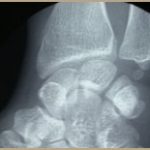

La maladie de Madelung est une anomalie qui touche avec prédilection les deux poignets et de façon asymétrique et se caractérise par une déformation à type de « subluxation antérieure spontanée et progressive du poignet » et une subluxation postérieure de l’extrémité du cubitus aboutissant à un radius courts et incurvés et un cubitus long limitant la mobilité du poignet et du coude. Elle est plus fréquente chez les filles et peut être congénitale ou acquise.

La maladie est due à une désorganisation de la croissance de l’épiphyse du radius, qui provoque son incurvation et une soudure du cartilage de conjugaison (épiphysiodèse) prématurée, avec un retard de développement du cubitus et des parties antérieures de l’épiphyse radiale inférieure.

Le diagnostic est évoqué à l’examen clinique et confirmé par la radiographie de l’avant-bras et du poignet.